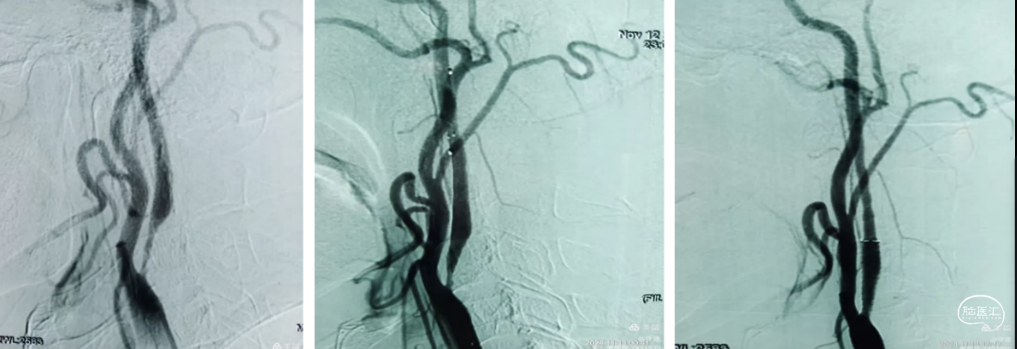

球囊穿梭:8F导引导管到达颈总动脉远端,微导丝携带微导管通过颈内起始部闭塞,2.5*15mm冠脉球囊扩张闭塞部,泄压的同时辅助6F中间导管通过狭窄到达C1以远。

踹马桶抽吸清理颈内动脉滞留血液:清理颈内滞留血液,抽出0.5 cm大小血栓,微造影M1段有血栓残留。下图2、3、4

支架取栓开通远端血管:微导丝回头弯置于M2段,将微导管置于M2段,输送4*30 SLitaire支架,抽拉结合取栓后造影血管通畅,未见明确血栓逃逸。下图5

颈内动脉狭窄血管成形:

负压抽吸回撤中间导管与颈总动脉,造影显示颈内动脉C1段重度狭窄。在C1段置入5mm保护伞,通过保护伞导丝输送4*30球囊预扩张后植入8-6一40颈动脉支架。撤出保护伞。

撤出保护伞再次造影显示颈内血管又不显影了,考虑血管痉挛可能。泥鳅导丝导引6F中间导管在颈内动和支架内抽吸未抽出血栓,但血管再次通畅。

推注替罗非班10mL,罂粟碱30mg,等待15分钟造影血流通畅,结束手术。